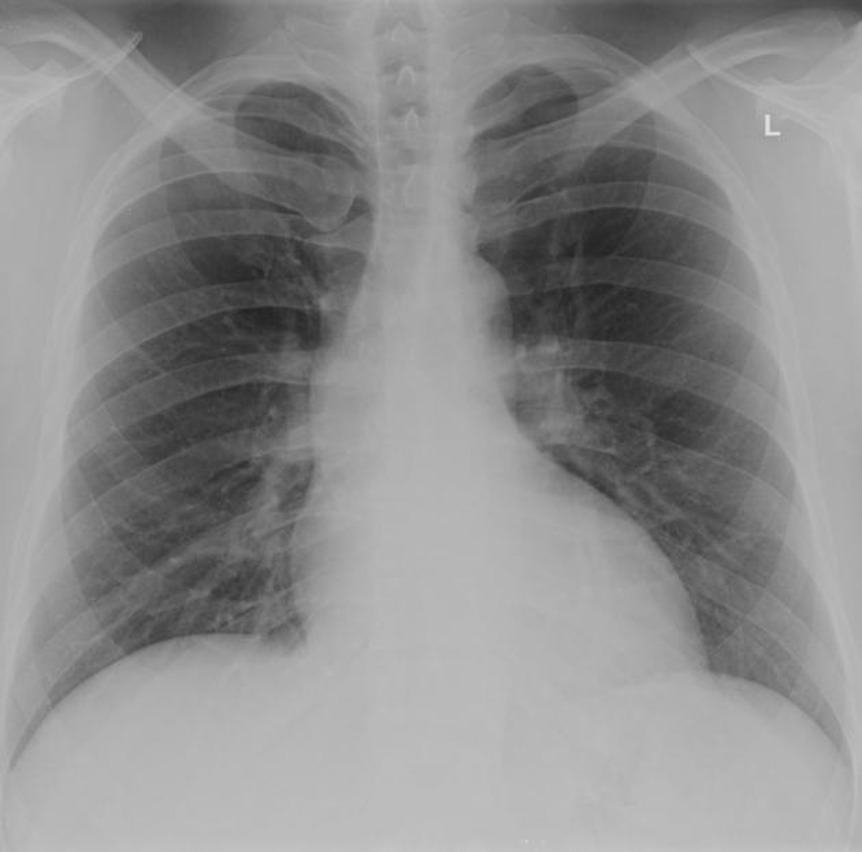

4. Please interpret the findings of this CXR for me

Case courtesy of RMH Core Conditions, Radiopaedia.org, rID: 27923

- Identifies bilateral equal lung expansion, with no evidence of focal consolidation or opacity. No pleural effusions. Mild cardiomegaly in keeping with PMH of HF.

- No evidence of pneumothorax, lung markings run to peripheries.

- Comments that trachea is central, borderline mild cardiomegaly.

- No gross evidence of bony injury or fracture.

- Identifies as a normal chest x-ray